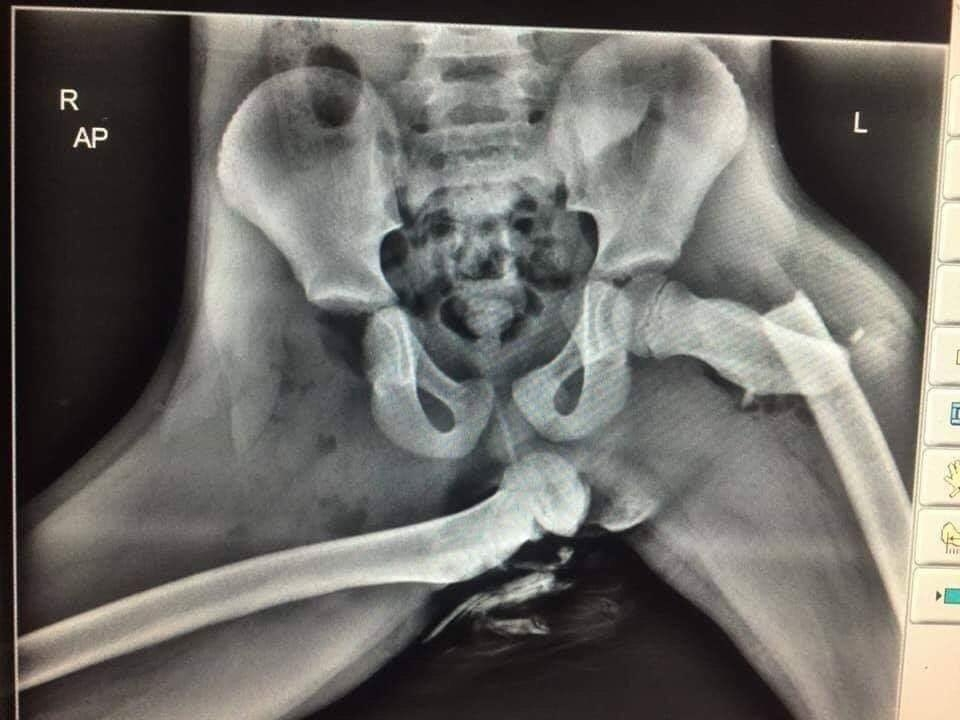

최근 영국 웨일즈에서 근무하는 이안 프라이스 경사는 자신의 트위터에 골반과 대퇴골, 다리뼈가 어긋나는 엑스레이 사진을 올렸다.

프라이스 경사는 “충돌 당시 대시보드에 발을 올려둔 조수석의 승객의 끔찍한 부상 사진”이라 전했다.

엑스레이의 주인공도 에어백의 여파로 코, 대퇴골, 발목 등에 심각한 부상을 입었다.

더불어 완전히 탈골된 오른쪽 대퇴골로 영구 장애 판정까지 받았다.